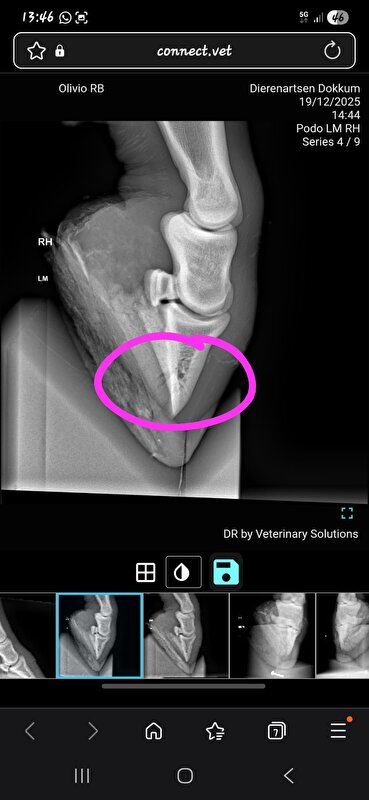

Mijn merrie is 1 januari 2025 kreupel uit de paddock gekomen. Wrs met een zooitje aan de ren geweest op de bevroren paddock, voet verkeerd neergezet of ergens tegenaan getrapt en ook hoefbeen gebroken. Echt gewoon domme pech geweest volgens de DA. Schijnt ook vaker voor te komen als de grond bevroren is.

Die van mij mocht na 6 maanden stalrust (wel echt op stal, en ook een rond ijzer) weer naar buiten. Ging toen ook over op een normaal ijzer. Zijn wel na zo'n 2,5e maand weer begonnen met stappen ad hand. Uiteindelijk heeft ze door een operatie aan mijn kant in totaal 8 maanden op "stal"rust gestaan (laatste 2 maanden in de opfok in een stal van 5x10m). Na 8 maanden de laatste foto's gemaakt, ijzer is er compleet onderuit gegaan, naar buiten toe opgebouwd (had dus al 2 maanden eerder gemogen maar ging niet op de stal waar ze toen stond) en sinds 1 november staat ze eindelijk weer op een normale pensionstal.

We hebben hier wel de 6 maanden volgemaakt en ik heb in het proces nog een keer een second opinion aangevraagd maar die gaven eigenlijk hetzelfde aan. Maar het zal wrs ook afhankelijk zijn van de grootte en de plek van de breuk en hoe vlot het hersteld.

Liep hier alleen helaas wel door tot het gewricht

Ben zelf dus vooral bang voor potentieel artrose op "jongere" leeftijd maar ook de second opinion was heel tevreden over de genezing dus hopelijk valt dat mee

DA heeft daar verder ook weinig over gezegd maar dat is echt iets wat de tijd uit zal moeten gaan wijzen. Dat die van jou dat niet heeft klinkt iig gunstig! Alhoewel ze bij jou miss wat sneller bang zijn dat dat hoekje kan gaan "verschuiven"?